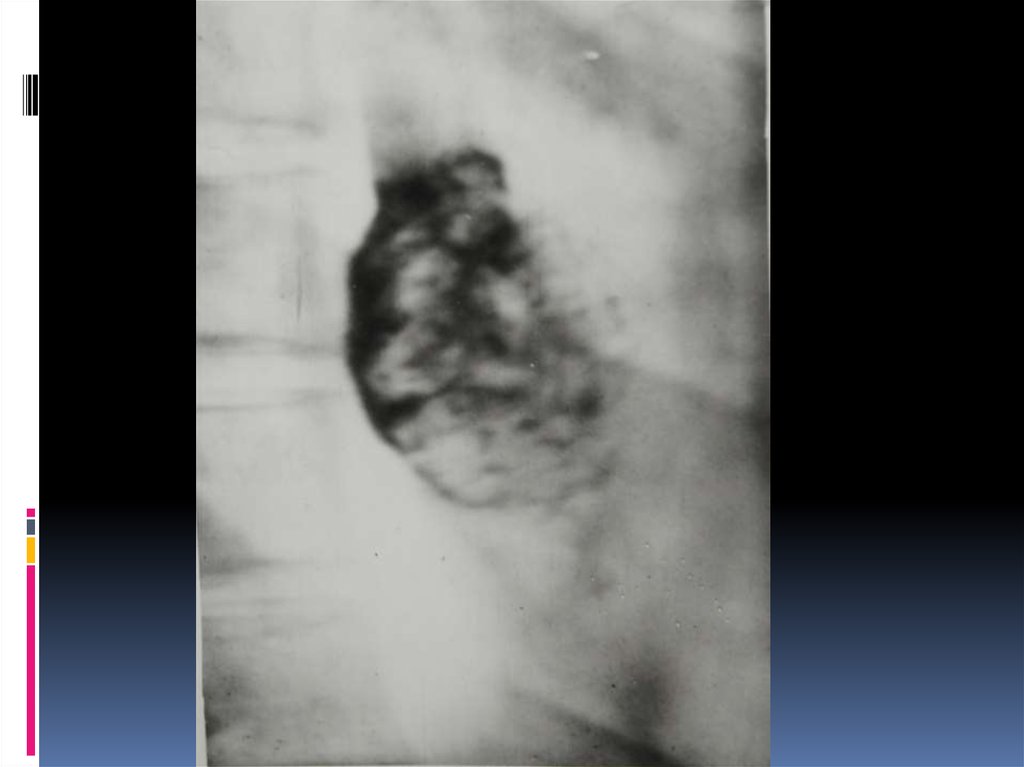

16. Рентгенодиагностика рака желудочно-кишечного тракта

Рентгенодиагностика

рака желудочнокишечного тракта

17. Классификация рака органов ЖКТ

1. Экзофитная форма:

2. Эндофитная форма:

узловая форма;

диффузноинфильтративная

форма;

полипоподобная

чашеподобная форма. инфильтративноязвенная.

3. СМЕШАННАЯ ФОРМА – 10-15%